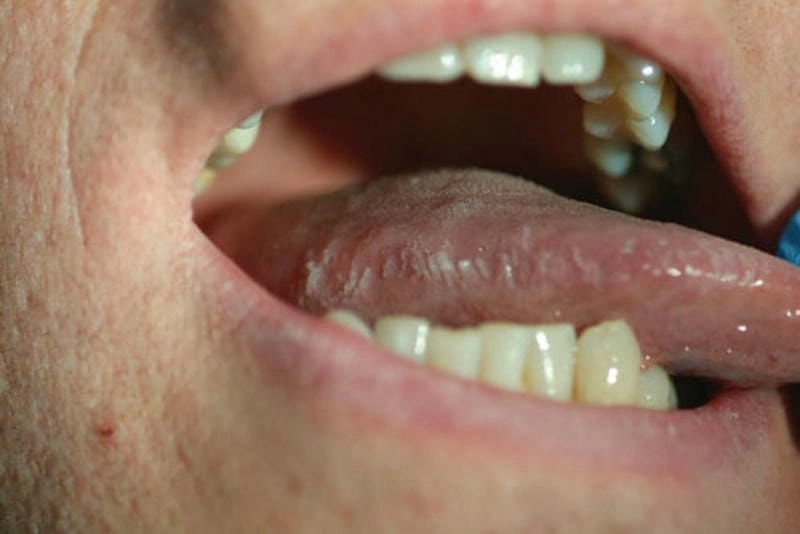

Hình ảnh bệnh bạch sản lưỡi là công cụ hữu ích giúp nhận biết sớm các tổn thương bất thường ở niêm mạc miệng. Việc quan sát các đặc điểm thay đổi trên lưỡi qua hình ảnh thực tế giúp người bệnh phát hiện và điều trị kịp thời, tránh biến chứng nguy hiểm.

Cảnh báo rợn người với hình ảnh bạch sản lưỡi: những mảng trắng kỳ lạ, gồ ghề xuất hiện như “vết sẹo ma” trên bề mặt lưỡi, tưởng chừng vô hại nhưng lại là dấu hiệu sớm của ung thư. Bạn sẽ không thể rời mắt khỏi loạt ảnh ghi lại từng chi tiết ghê rợn đến lạnh gáy, từ giai đoạn đầu mờ nhạt đến lúc loét sâu, khiến người xem không khỏi rùng mình.

Cú sốc thị giác từ bộ hình ảnh bệnh bạch sản lưỡi thật khiến ai xem cũng phải giật mình. Những bức ảnh zoom cận từng vùng tổn thương, ánh sáng lạnh lẽo và gam màu u ám gợi cảm giác đau đớn tột cùng. Không chỉ là tư liệu y học, đây còn là một tác phẩm nghệ thuật của sự thật tàn nhẫn, khiến người xem phải suy ngẫm về sức khỏe lưỡi của chính mình.

Qua việc phân tích hình ảnh bệnh bạch sản lưỡi, chúng ta có thể nhận biết dấu hiệu bệnh sớm và có phương án thăm khám phù hợp. Hãy chủ động kiểm tra sức khỏe răng miệng định kỳ để phòng tránh những biến chứng đáng tiếc từ bệnh lý này.